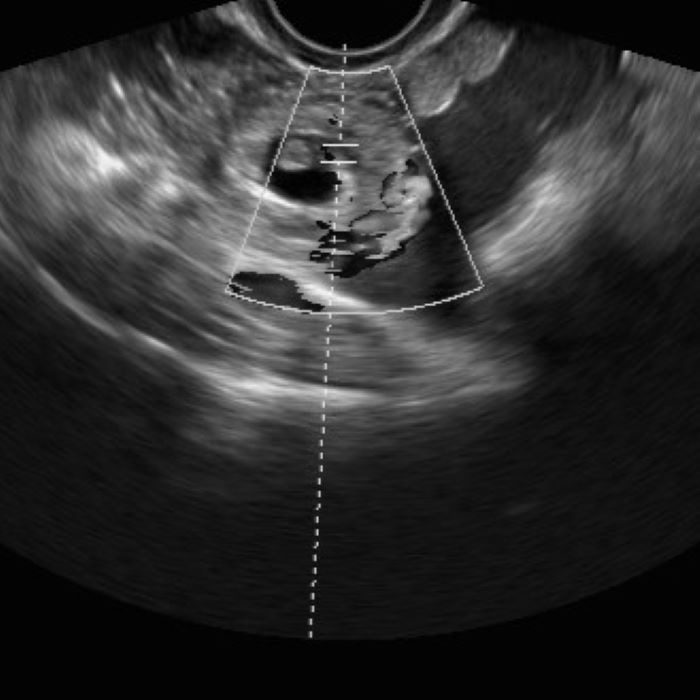

7 неделя внематочной

7 неделя внематочной 107 фото